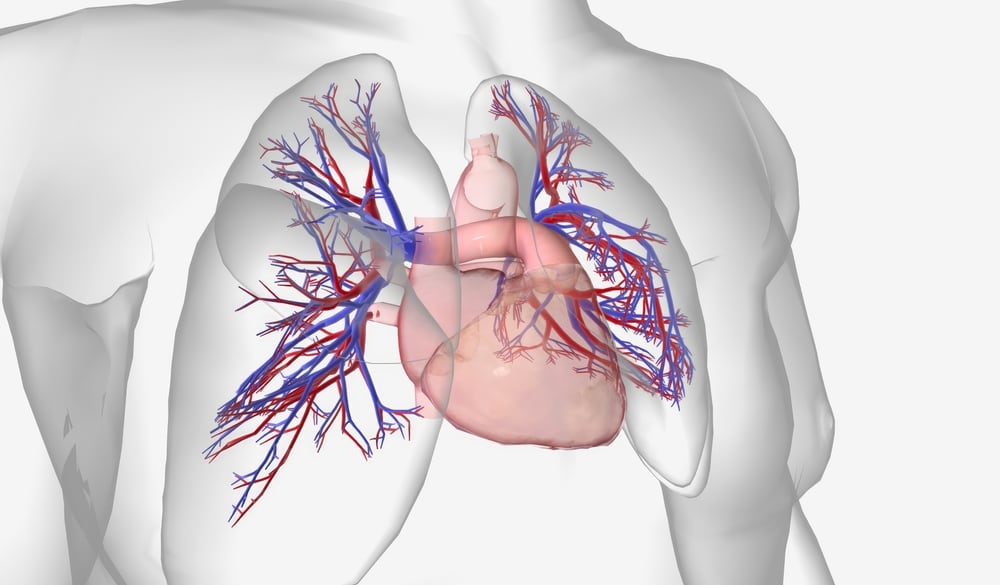

ACC/AHA guidelines are reshaping US payer policies, expanding coverage and access to breakthrough cardiovascular therapies like SGLT2 and PCSK9 inhibitors. But costs, red tape, and uneven access still stand in the way.